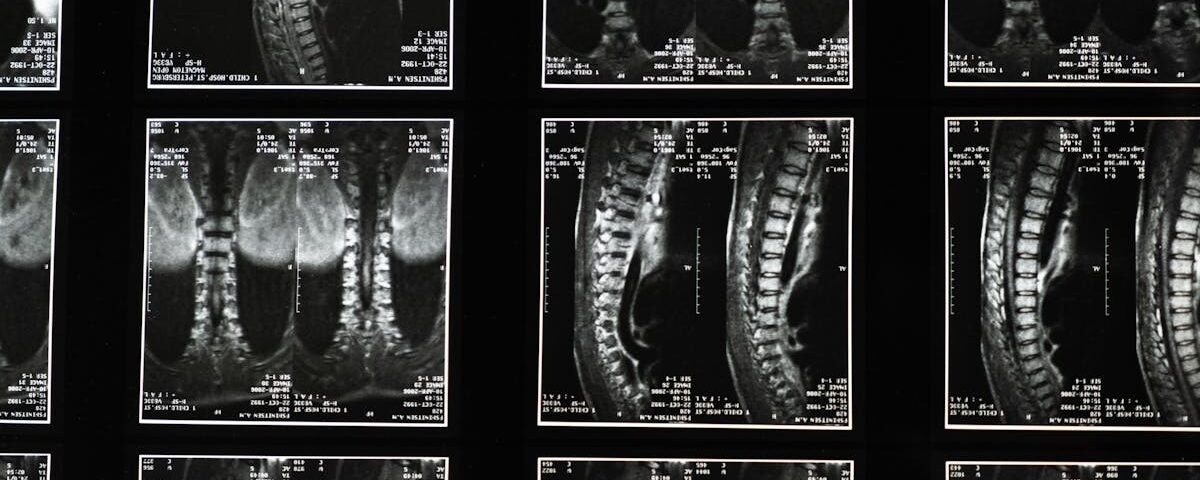

Quels examens sont nécessaires avant de commencer un traitement de décompression pour la sciatique?

Une IRM ou une radiographie est généralement recommandée pour évaluer l’état de la colonne vertébrale.